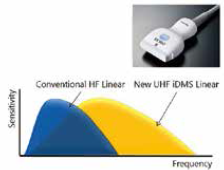

Датчик i-серії PLI-2004BX має надвисоку частоту (центральна: 24 МГц) і широкий діапазон частот, що забезпечує чудову просторову роздільну здатність. Розширений частотний діапазон значно покращує якість зображення.

Малюнок 1. Надвисокочастотний лінійний датчик PLI-2004BX